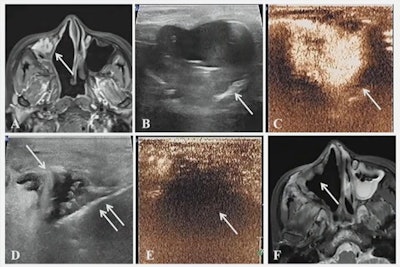

A case presented at the ARRS annual meeting shows the results of successful microwave ablation (MWA) treatment for a 39-year-old female with metastatic fibrosarcoma of the right axillary sinus.

Jiang also presented some case reports, including one case that described where a 39-year-old was treated for metastatic fibrosarcoma of the right maxillary sinus. Images taken 12 months after MWA showed that the tumor had disappeared.

In another case, MWA was used for postoperative rib metastasis of a gastric stromal tumor. Ultrasound images acquired after MWA showed no enhancement and the patient reported no pain.